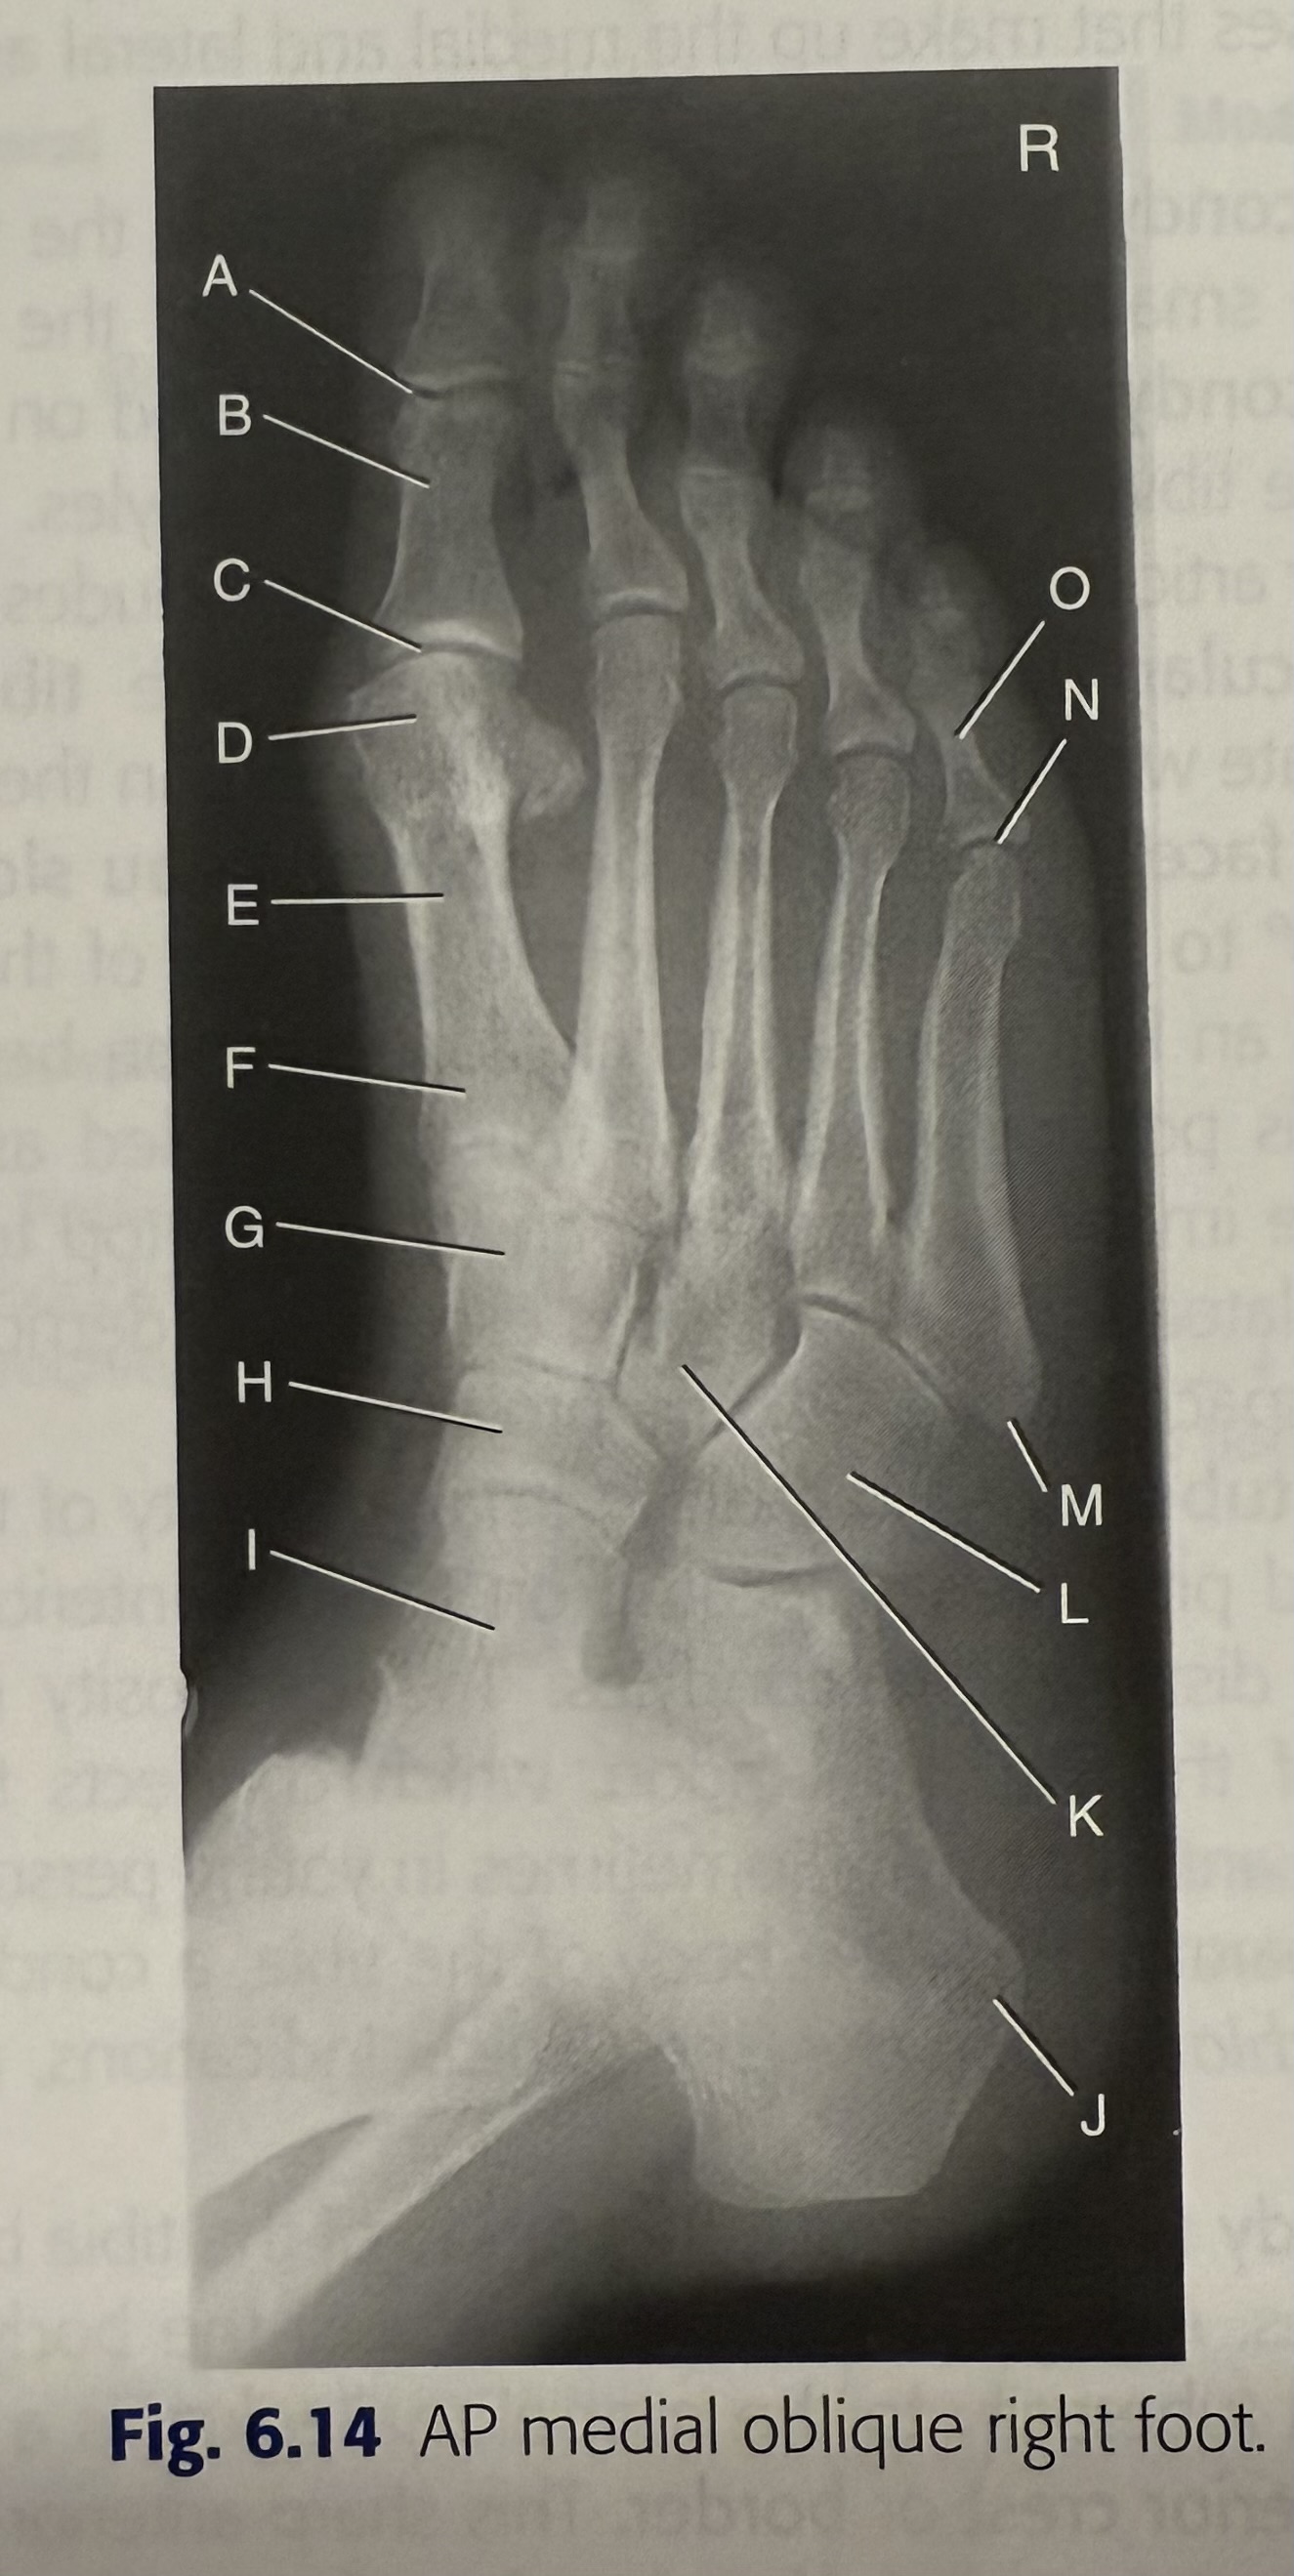

New cards

<p>F</p>

F

tibial plafond

12

<p>G</p>

G

medial malleolus

13